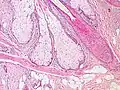

Sebaceous glands are found in hair-covered areas, where they are connected to hair follicles. One or more glands may surround each hair follicle, and the glands themselves are surrounded by arrector pili muscles, forming a pilosebaceous unit. The glands have an acinar structure (like a many-lobed berry), in which multiple glands branch off a central duct. The glands deposit sebum on the hairs and bring it to the skin surface along the hair shaft. The structure, consisting of hair, hair follicles, arrector pili muscles, and sebaceous glands, is an epidermal invagination known as a pilosebaceous unit.[4]

Sebaceous glands.